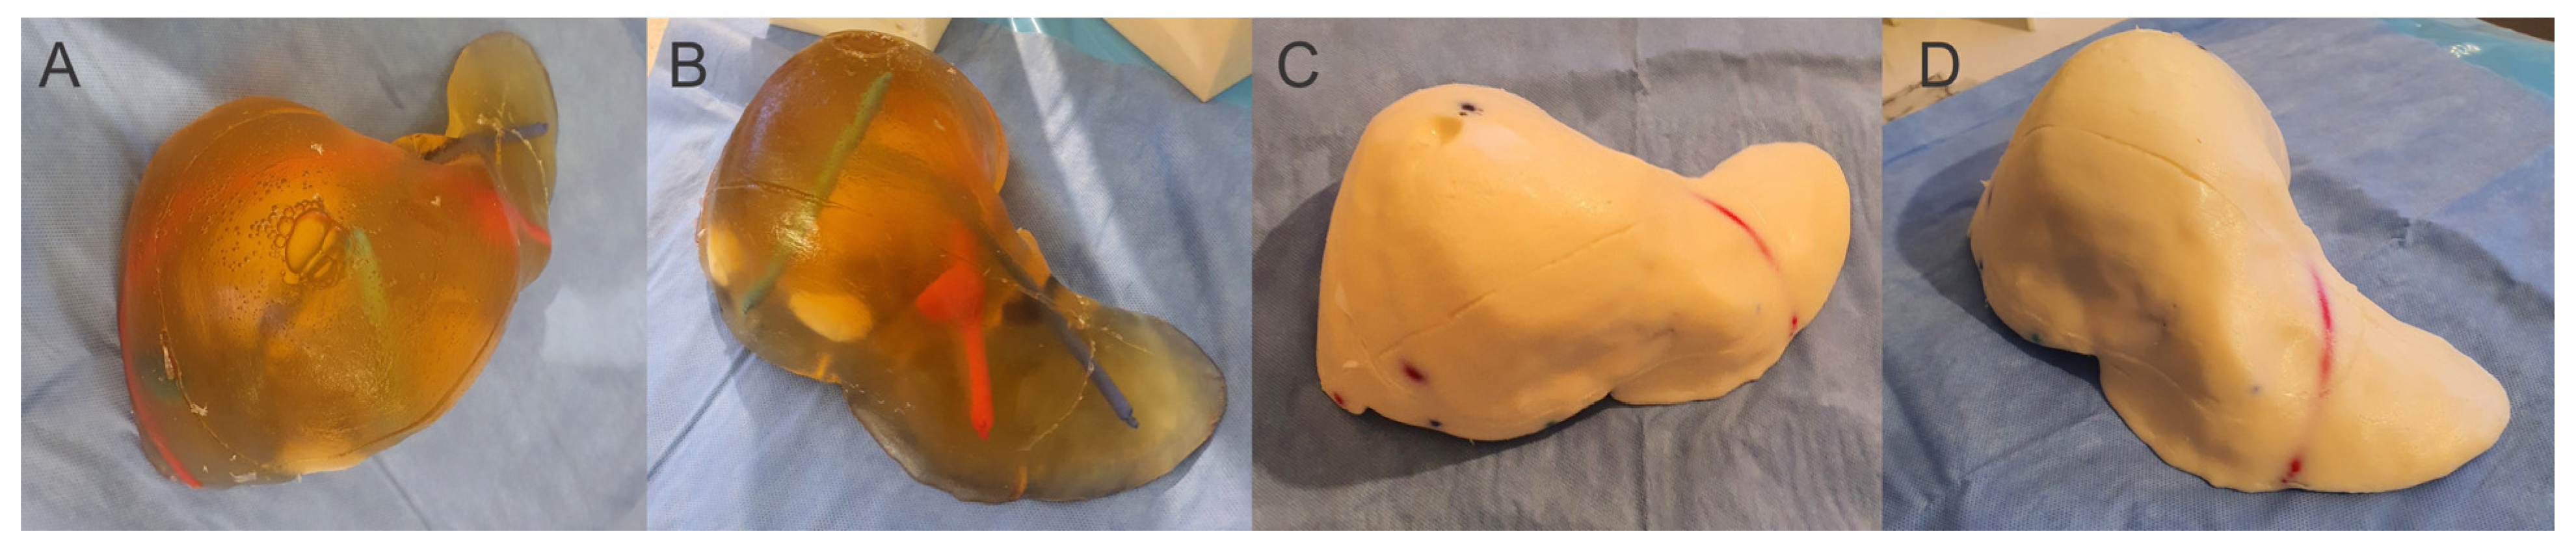

2. Materials and Methods

3. Results

4. Discussion